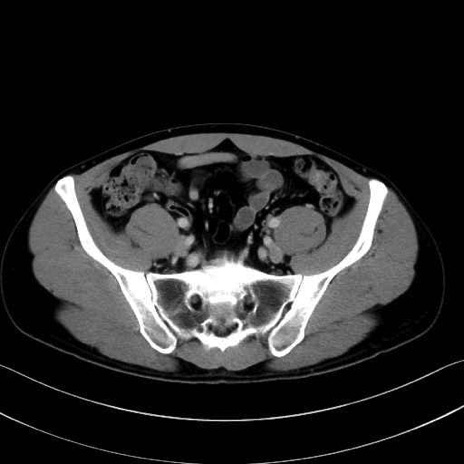

梨状筋(piriformis muscle) のCT画像の解剖

内閉鎖筋 (Obturator internus)

外閉鎖筋 (Obturator externus)